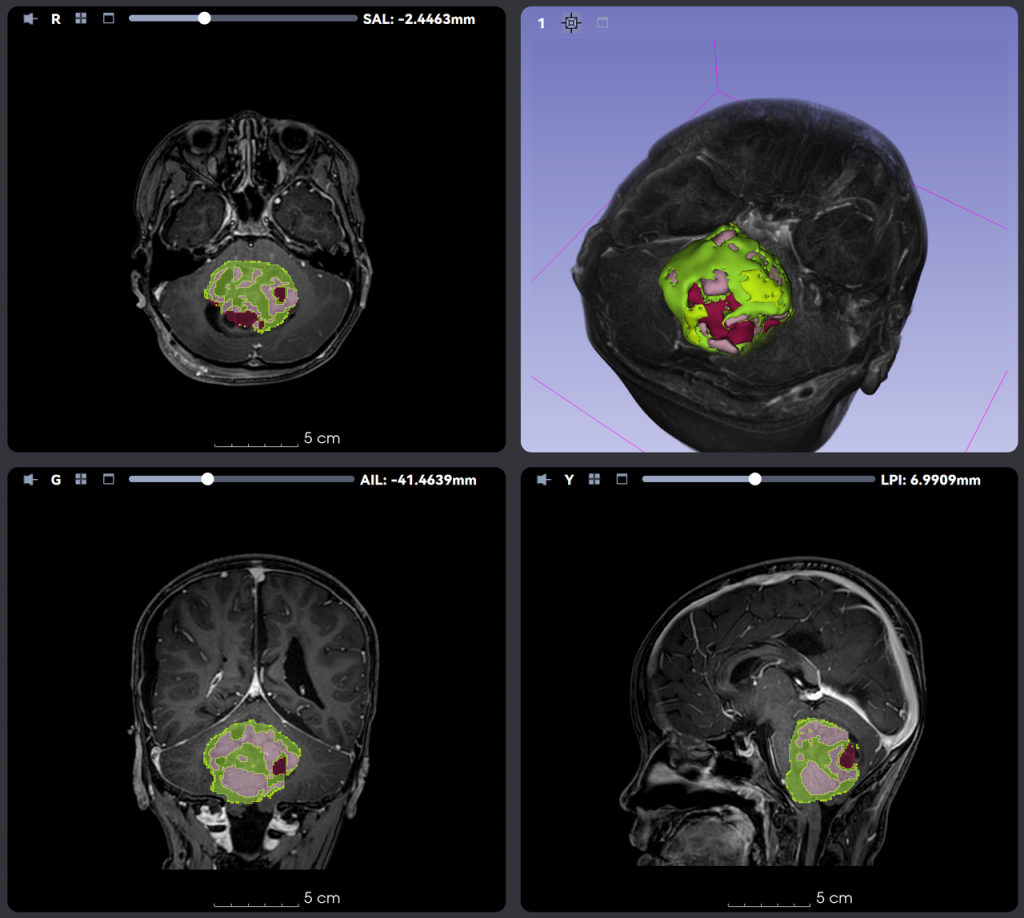

全年龄段AI脑肿瘤智能分割与分类

算法基于覆盖儿童、成人与老年群体的多中心数据集训练,在不同年龄段人群中均表现出优异的稳定性与准确性。